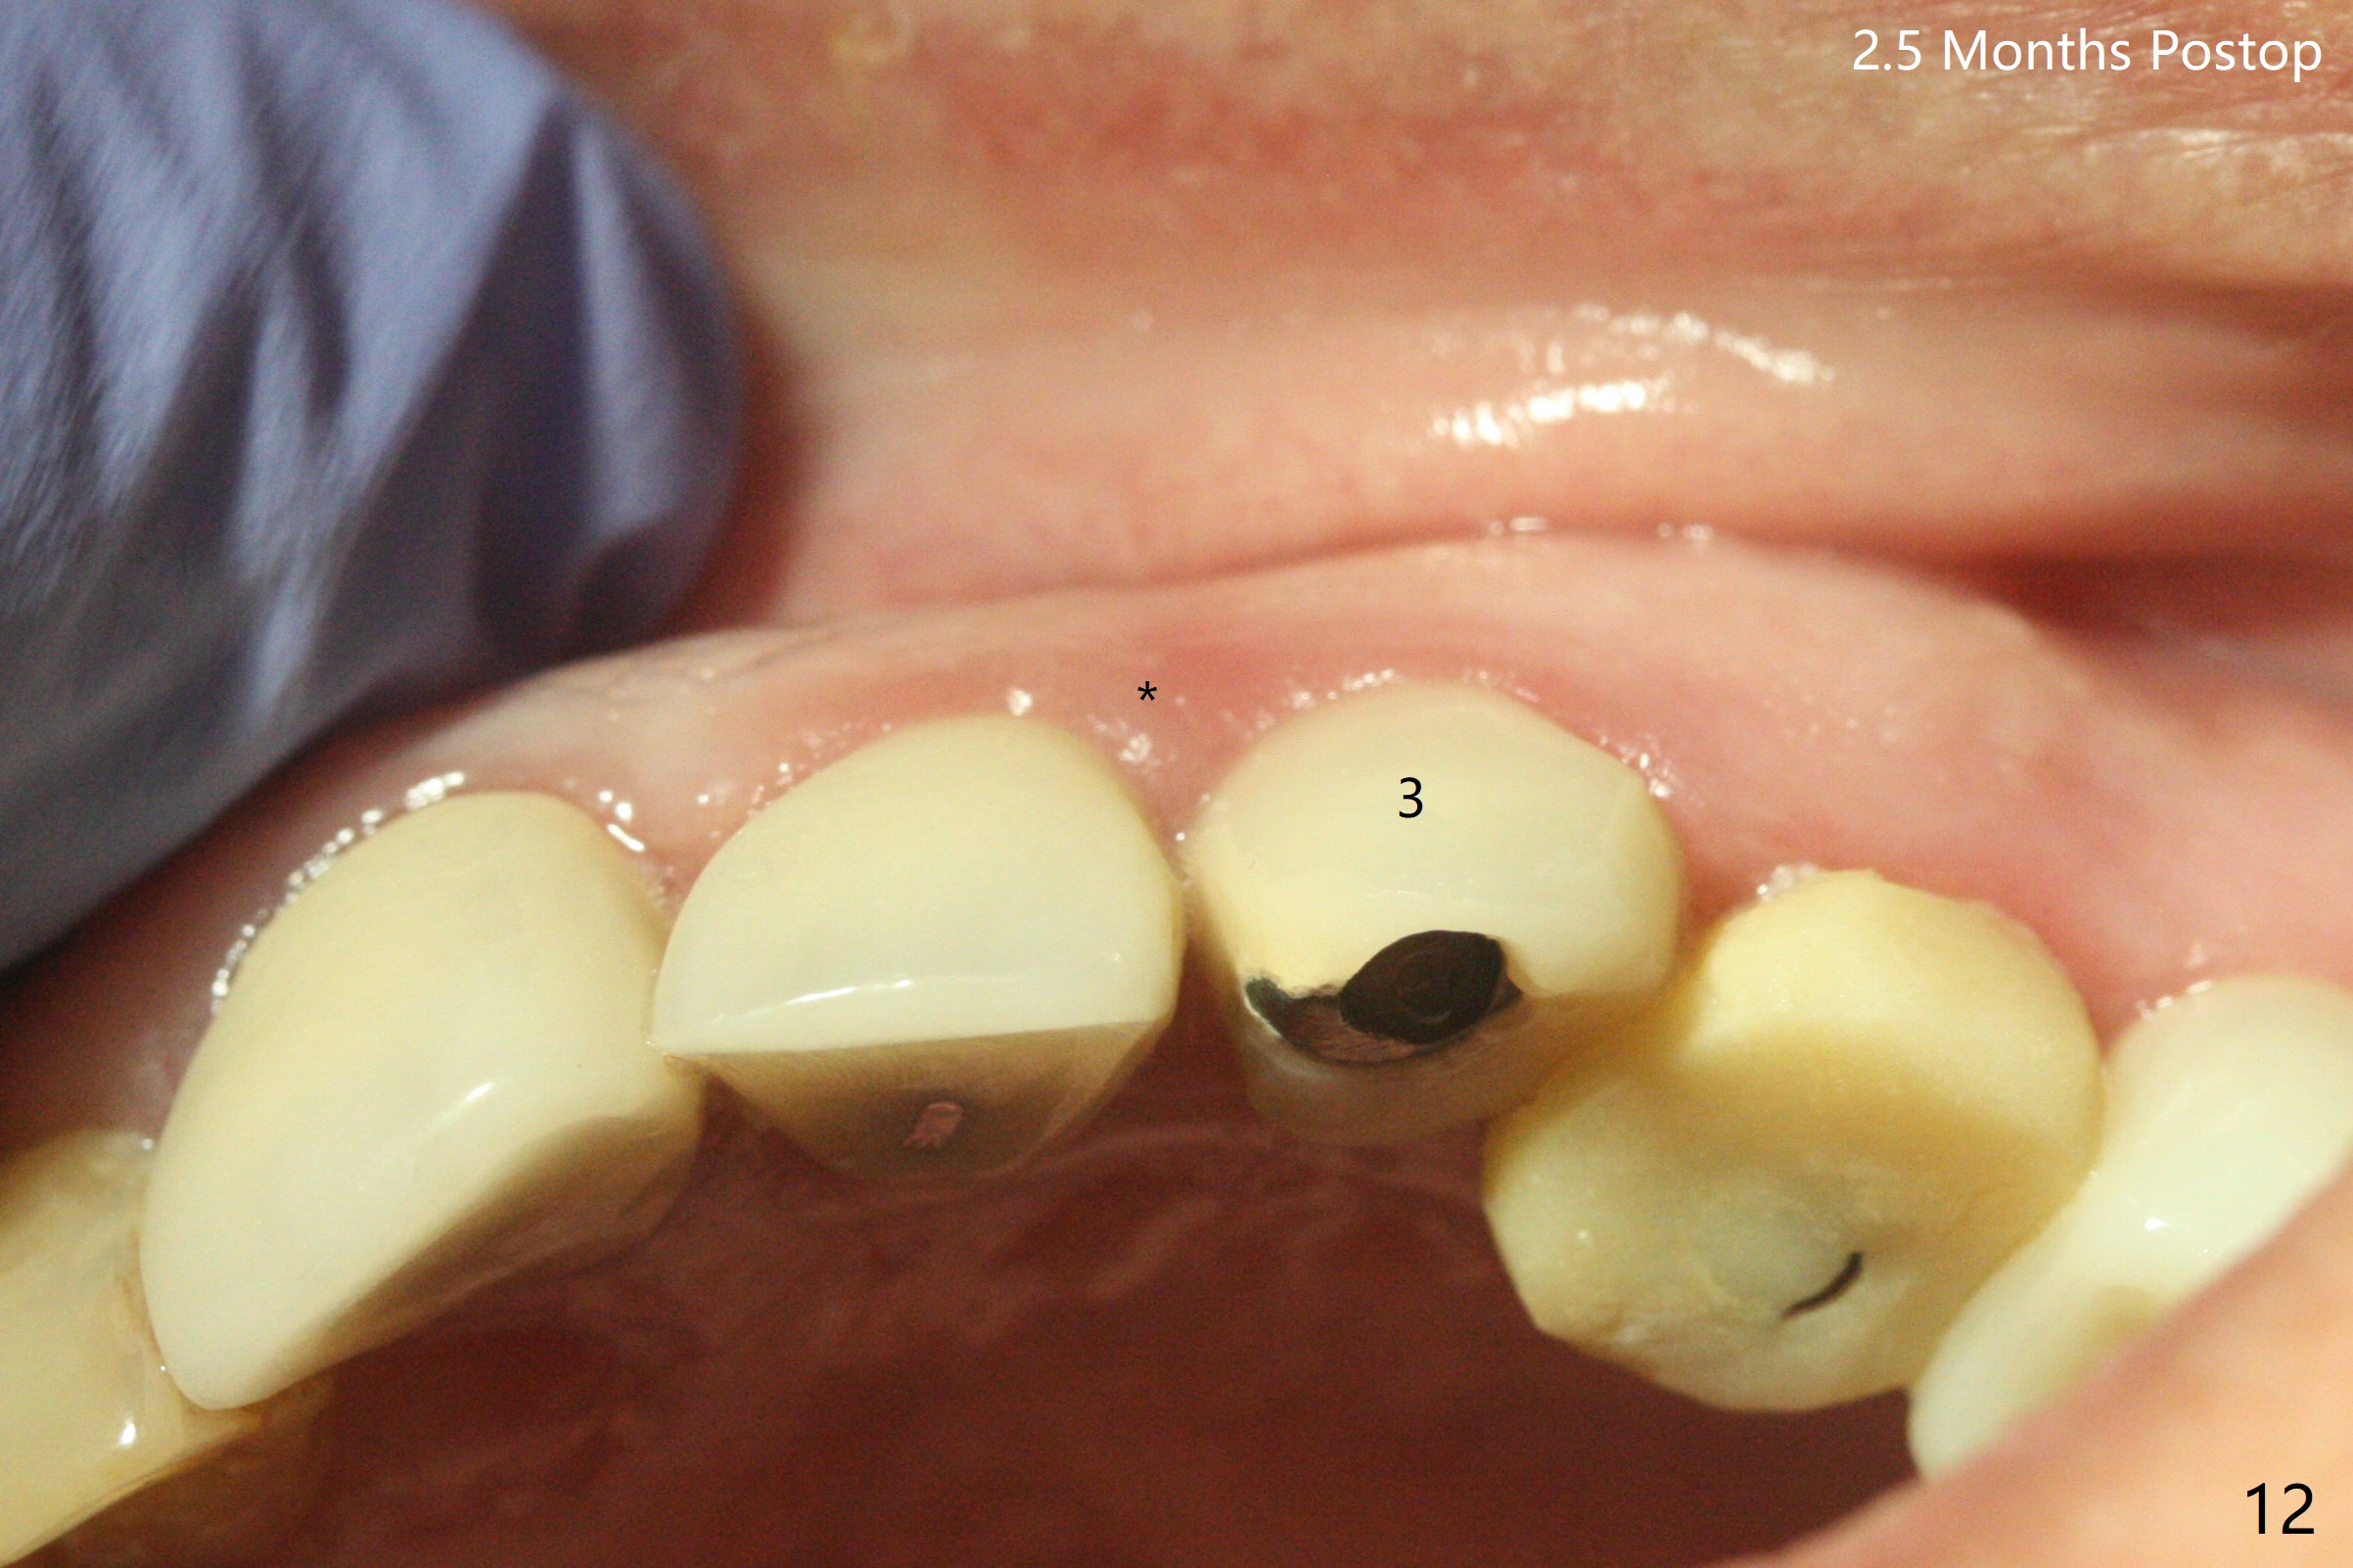

52岁女左上4颊侧牙龈显著肿胀(图一:*(颊侧骨板缺失))伴有瘘道(<),拔除前,在3植牙牙冠切缘舌侧形成开口(图二:*,准备纠正基台不全就位(<);4初步钻洞不正。改变钻头方向后(图三),完成植体放置(图四),并且安置修复基台(4.5x4(2))。磨去3牙冠近中面(图六:*),牙冠和基台反时针旋转(图六:弯箭头),基台完全就位(图四:箭头),调𬌗后,制作4临时牙冠(图六),放置后者前,覆盖半张PRF膜(促进下面粘性骨粉愈合)。图五,六颊侧隆起是因为下面放置许多粘性骨粉。图七是术前CT3D图像(冠状切面),显示颊侧(B),腭侧(P)牙根。拔牙后显示中隔(图八:S),植体植入腭侧窝(图九:绿色),四面骨质包绕,包括中隔;为了修复颊侧骨板,首先放置半张PRF膜(红色)紧贴颊侧骨板腭侧/牙龈,防止骨粉从瘘道流失,然后放置粘性骨粉(图十:粉红色)。术后2.5月3颊侧牙龈仍然红肿(图十一,十二:*),可能与基台袖太短有关(2毫米,图二至四),所以更换袖3毫米的基台(图十三)。术后四个月(牙冠粘固)3颊侧牙龈炎症明显减退(资料没有显示)。术后2.5月4颊侧骨板没有塌陷(图十二,与术后即刻对比(图六))。3基台放置太颊侧,所以在牙冠腭侧制作小的开口(图十四:>),让多余粘固剂流出。取模前3螺丝就拧紧(35Ncm),而4由于有大的开口,粘固后才拧紧(30Ncm)。两个邻牙其中一个可以取出,容易去除另外一个牙冠残余粘固剂。